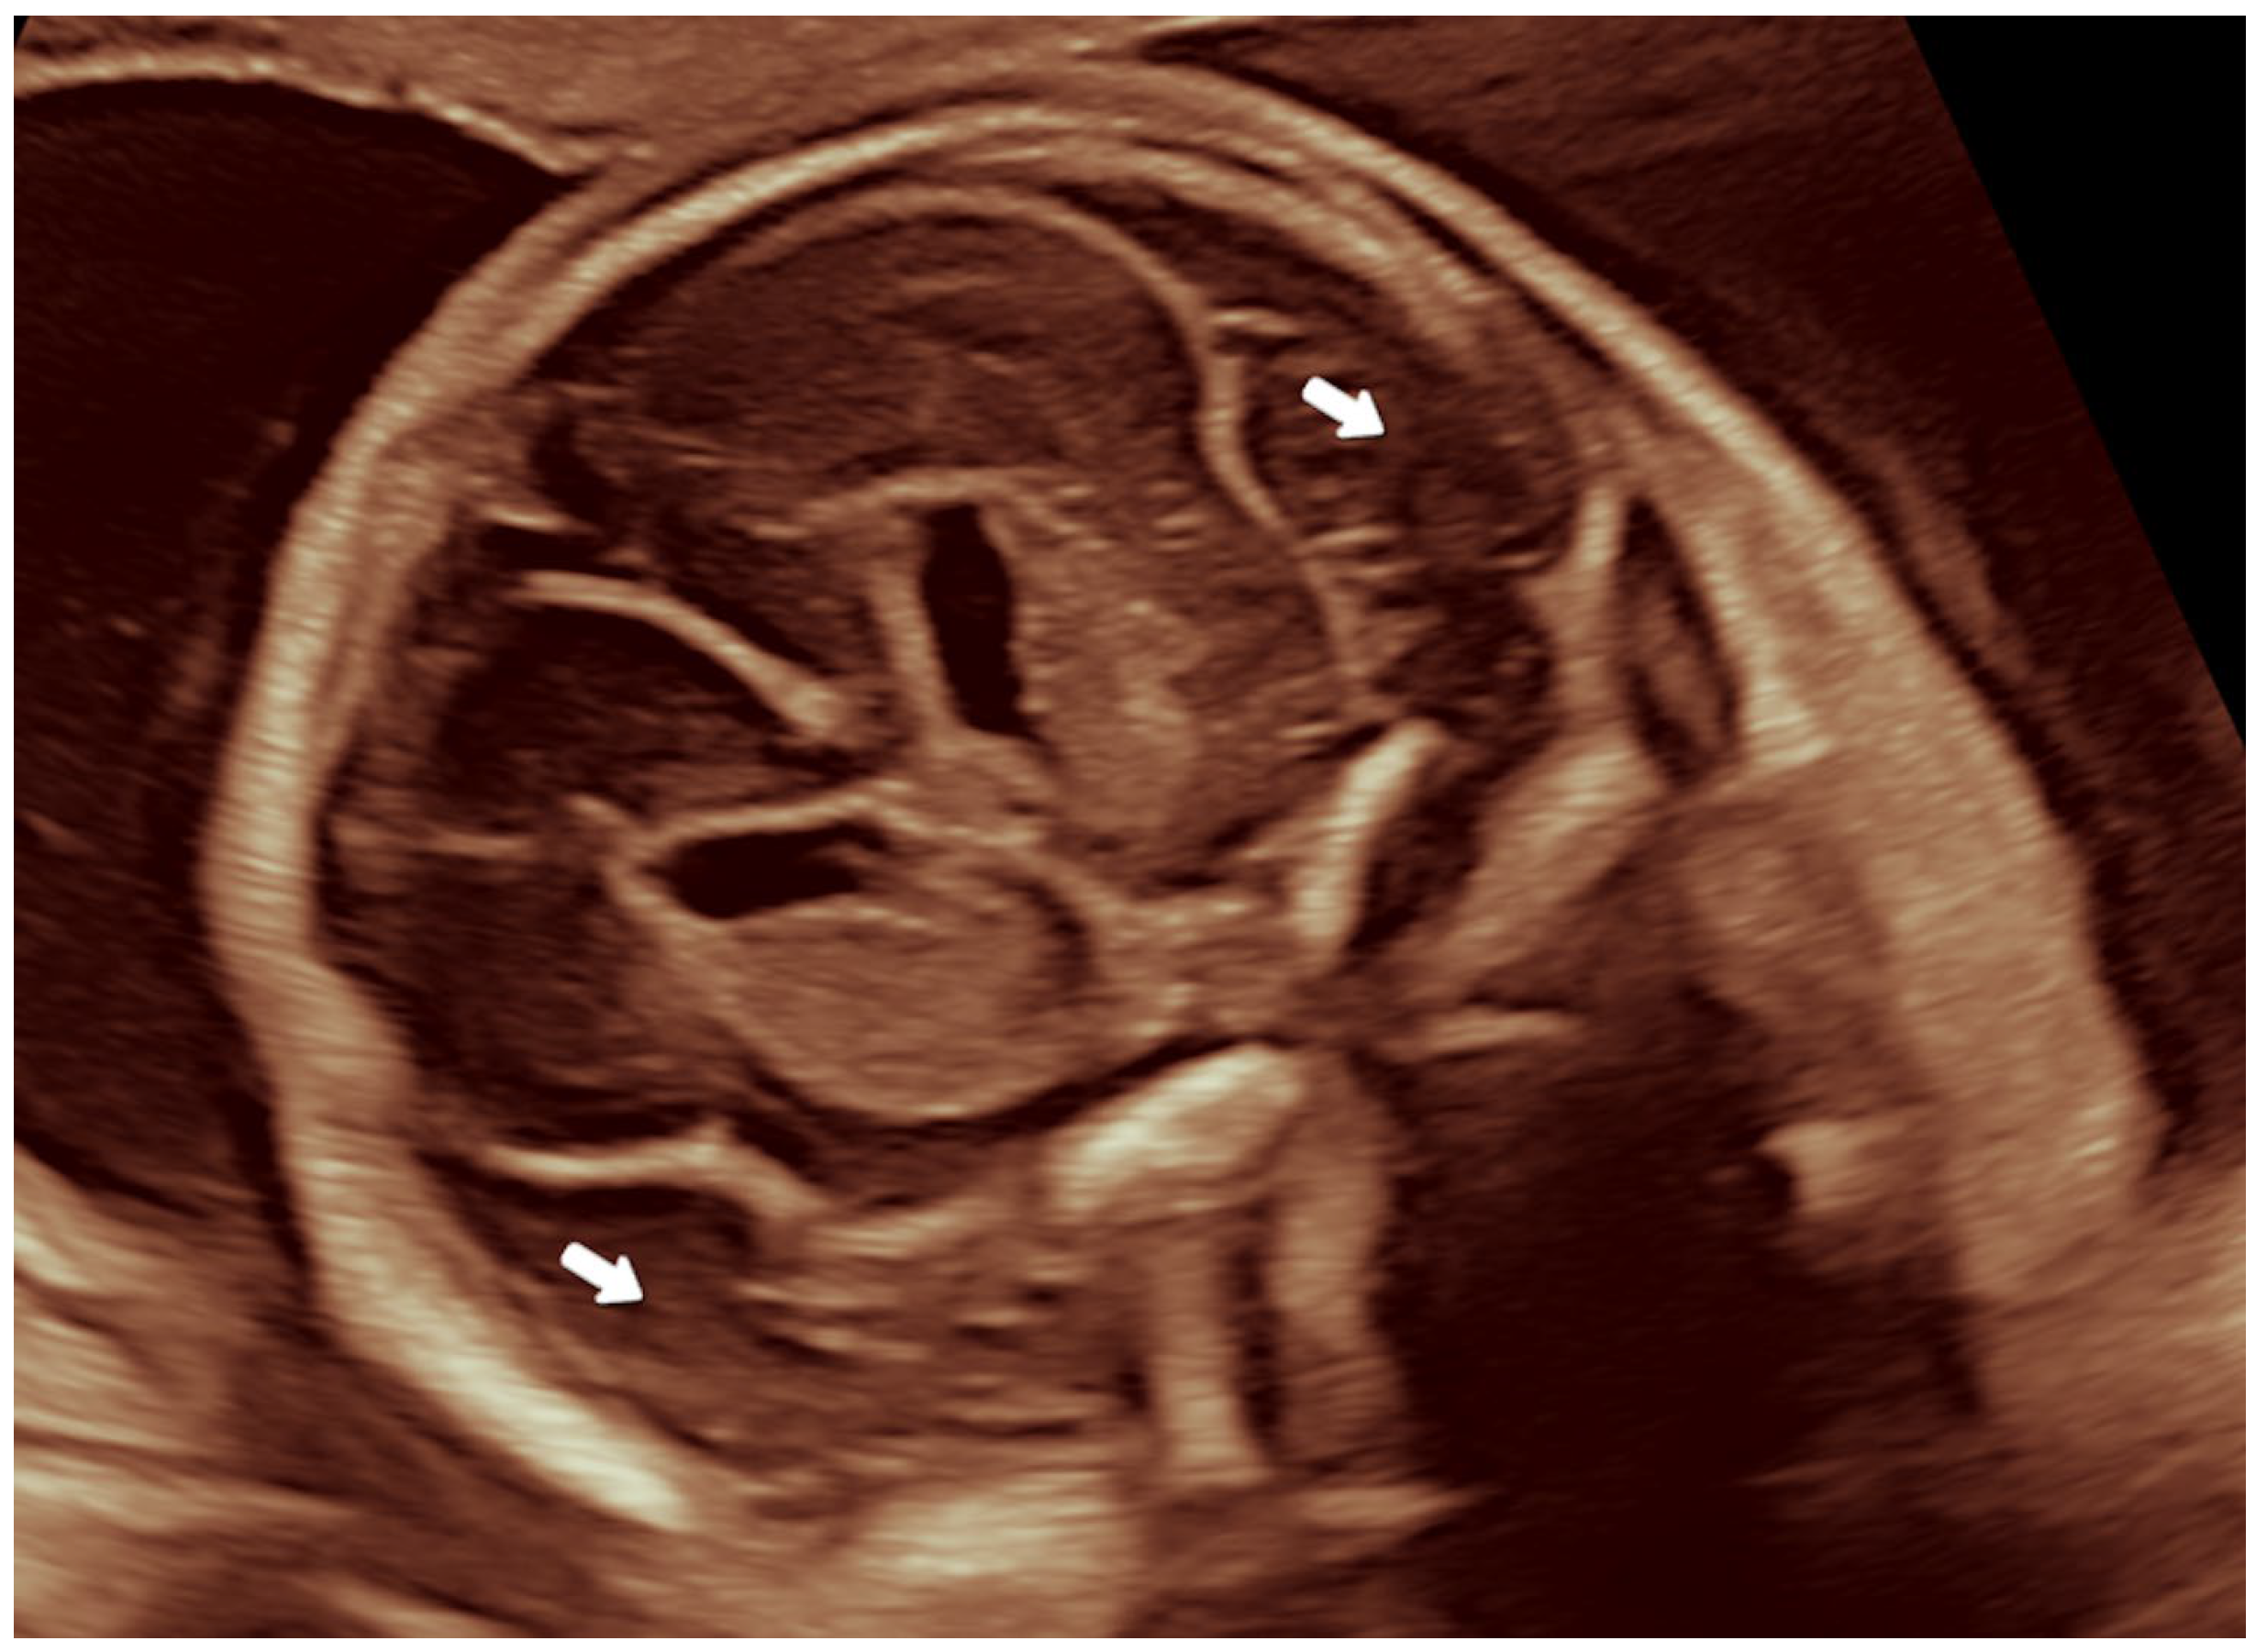

2.2.2. Ultrasound Findings